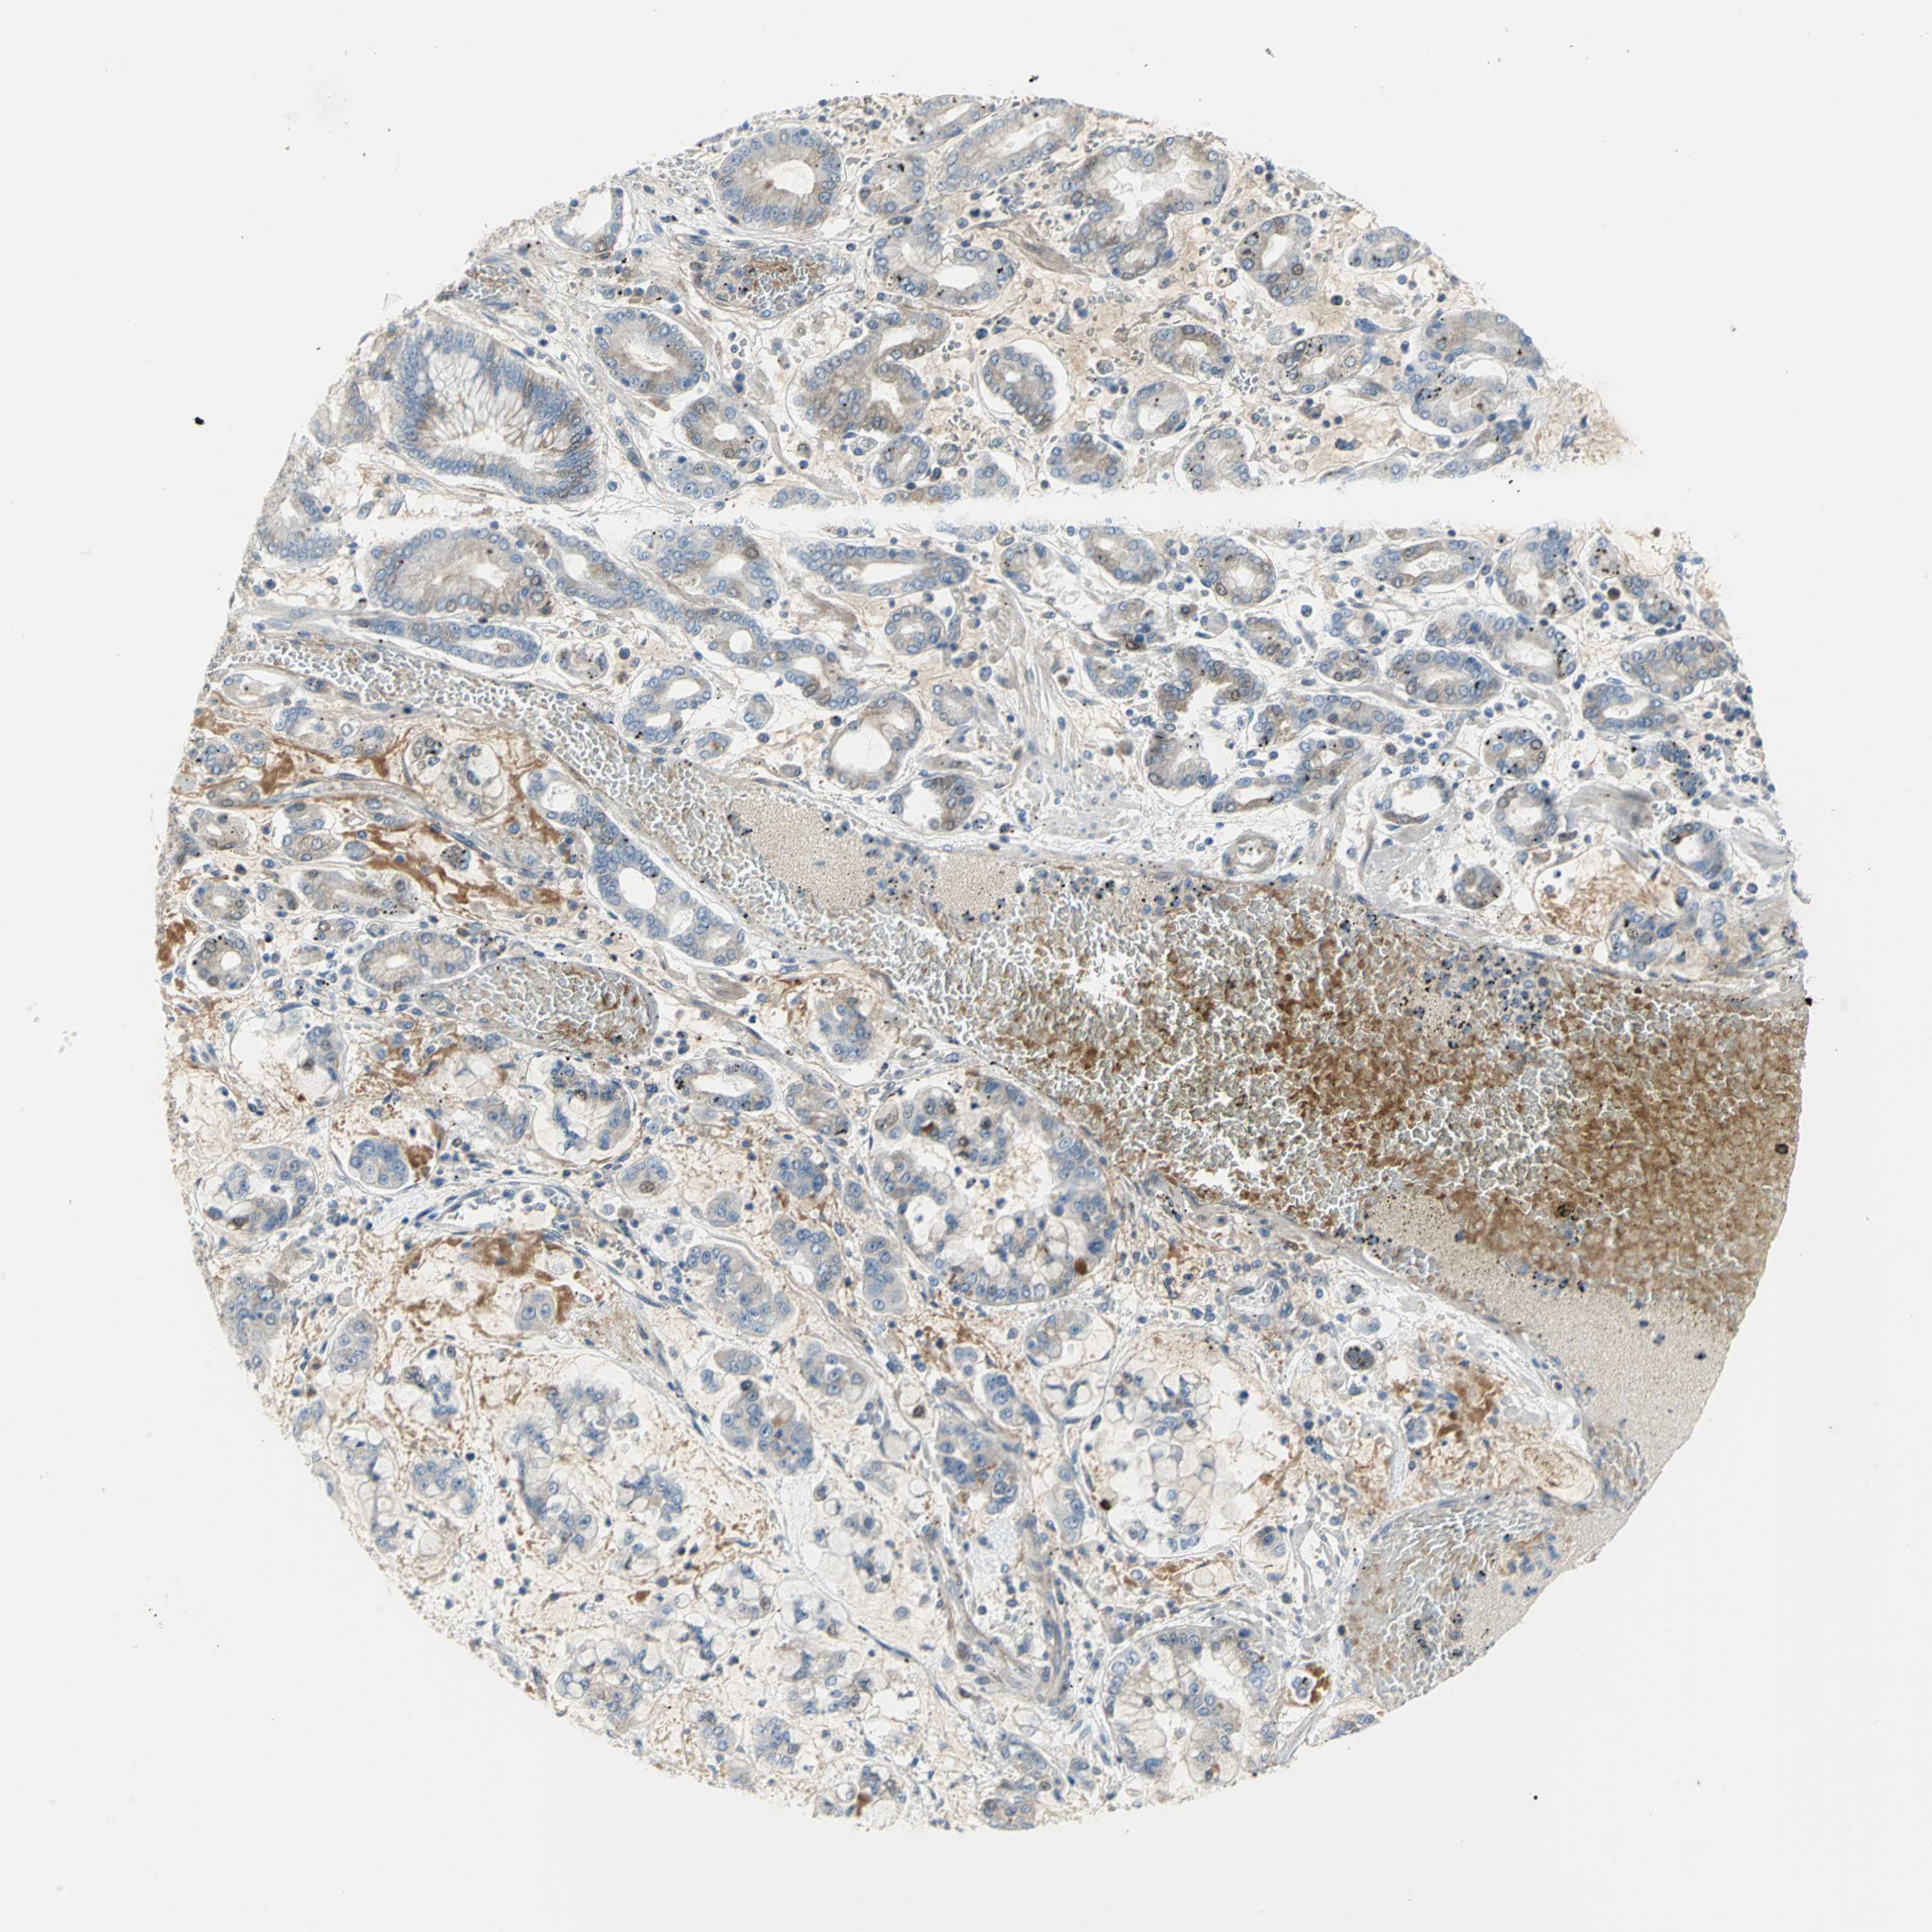

STOMACH CANCER - Protein expressioni

A mouse-over function shows sample information and annotation data. Click on an image to view it in a full screen mode. Samples can be filtered based on level of antibody staining by selecting one or several of the following categories: high, medium, low and not detected. The assay and annotation is described here.

Note that samples used for immunohistochemistry by the Human Protein Atlas do not correspond to samples in the TCGA dataset.

Antibody stainingi

Antibody staining in the annotated cell types in the current human tissue is reported as not detected, low, medium, or high, based on conventional immunohistochemistry profiling in selected tissues. This score is based on the combination of the staining intensity and fraction of stained cells.

Each image is clickable and will lead to virtual microscopy that enables deeper exploration of all samples and also displays staining intensity scores, fraction scores and subcellular localization as well as patient and tissue information for each sample.

Antibody HPA004098

Staining

High

Medium

Low

Not detected

Intensity

Strong

Moderate

Weak

Negative

Quantity

>75%

75%-25%

<25%

None

Location

Nuclear

Cytoplasmic/membranous

Cytoplasmic/membranous,nuclear

Adenocarcinoma, NOS

Adenocarcinoma, High grade